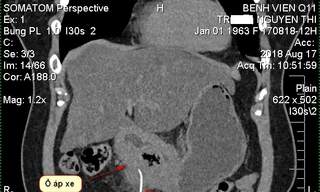

TPO - Hội chứng Pica là một rối loạn ăn uống trong đó người bệnh có sự thèm ăn và ăn những thứ không phải thực phẩm, chẳng hạn như đất đá, phân động vật, tóc, giấy, đồ vật kim loại, hoặc các vật liệu khác không có giá trị dinh dưỡng.